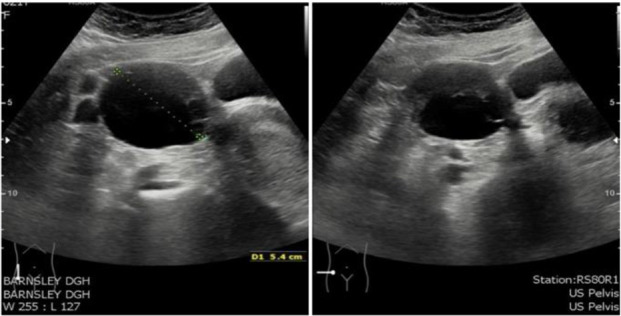

Case presentation: A 16-year-old nulliparous female was admitted with persistent lower abdominal pain and bloating. A pelvic magnetic resonance imaging showed large bilateral cystic and multiloculated adnexal masses arising from her ovaries. Her tumor markers were normal. The patient underwent three seperate ovarian cystectomies over a seven-year period from the age of sixteen due to recurrent large bilateral benign ovarian mucinous cystadenomas. Repeated histological examinations were the same after each case. Given her age and the history of multiple ovarian surgeries, she was referred to the fertility clinic to explore options for oocyte cryopreservation.